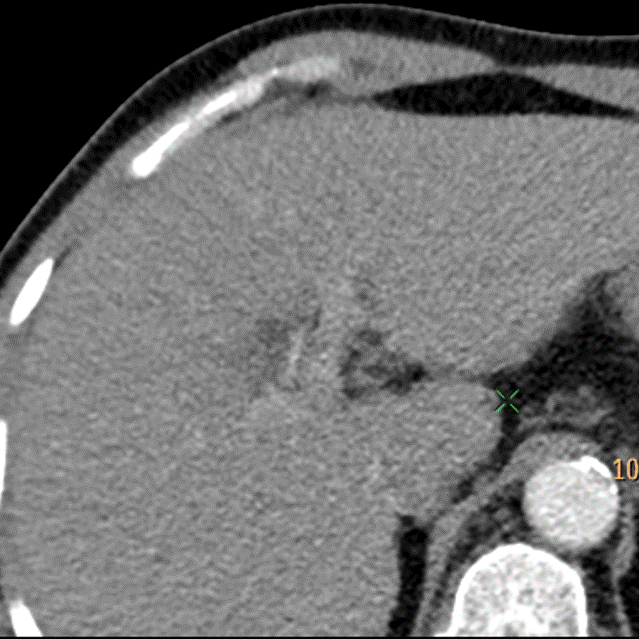

Portal venous phase, conventional phase. You cannot assess for washout, which is one of the major criteria for LiRADS.

Portal venous phase, 40 keV mono-E. The washout is obvious!